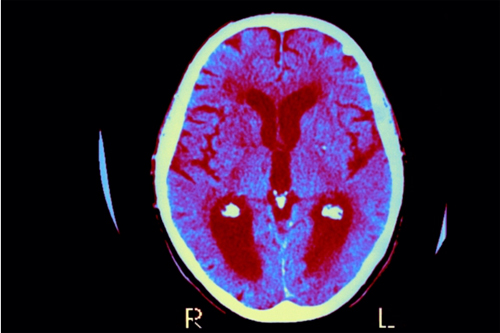

阿尔茨海默病是一种毁灭性的疾病,目前已有超过500万美国人因此丧失了认知能力和记忆功能,而科学家们一直以来都对其发病根源感到困惑不已...

人们大脑对入侵微生物的防御会导致阿尔茨海默氏症,这表明疫苗能够预防这一状况...

近日,由中科院广州生物医药与健康研究院胡文辉课题组设计与合成,由华南新药创制中心主导临床前研究,共同开发的抗阿尔茨海默症1.1类新药 - GIBH130及其片剂获得了国家食品药品监督管理局(CFDA)颁发的“药物临床试验批件”...